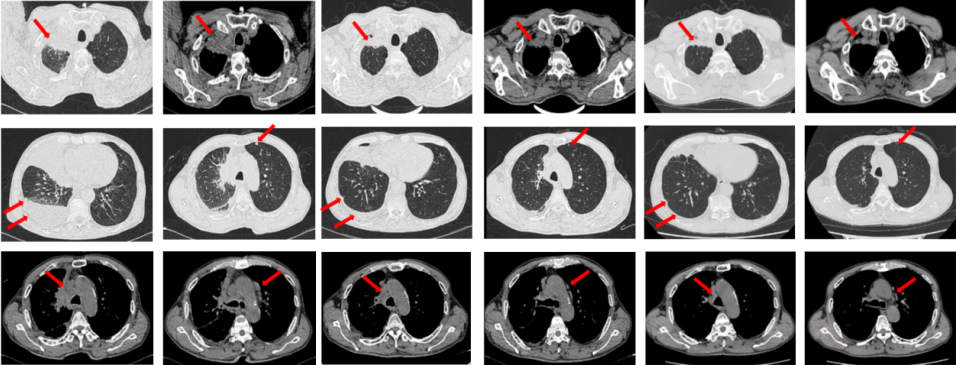

2022年7月至2022年11月行贝伐珠单抗联合培美曲塞/顺铂方案治疗6周期,2周期后评效PR,4周期后评效SD-(如图1)。第6周期治疗结束后患者自行终止治疗。

图1:由左至右分别展示基线(A.)及一线治疗后改变(B.和C.)。红色箭头指示病灶位置,由上至下分别为右肺肿物、右侧胸膜转移病灶及胸腔积液、左侧胸膜转移病灶、多发纵隔淋巴结肿大。

2023年3月患者因咳嗽伴胸闷复查出现全面PD。2023年3月-2023年4月重启原方案贝伐珠单抗联合培美曲塞/顺铂治疗2周期。2023年5月复查评效PD。行左锁骨上淋巴结穿刺,病理回报:左锁骨上见异型细胞,考虑为癌可能性大。组织NGS基因检测:MET基因扩增(变异倍数)2.0倍,TP53错义突变,PD-L1(22C3):TPS 75%。2023年5月-2023年8月改行替雷利珠单抗联合紫杉醇脂质体治疗4周期,2周期后评效SD。(如图2)

图2:A.代表一线治疗停药后病情进展,右肺上叶肿物、右侧胸膜转移灶及纵隔淋巴结较前增大、增多,右侧胸腔积液较前增多;B.原方案重启后复查评效右肺上叶肿物及纵隔淋巴结较前略饱满,右侧胸腔积液较前明显增多;C.更改二线治疗方案后整体病灶较前无显著变化。

2023年9月复查评效PD。成功入组“一项开放、多中心对比谷美替尼与多西他赛在既往接受免疫治疗和含铂双药化疗后进展的驱动基因阴性且伴有MET扩增的局部晚期或转移性非小细胞肺癌患者中的随机对照III期临床研究”。成功随机到试验组,口服谷美替尼至2024年10月,期间复查最佳评效PR。

图3:A.二线治疗后病情进展,右肺上叶新发肿物较前明显增大,新发无症状脑转移病灶;B.经谷美替尼(300mg po qd)治疗3个月后复查肺内病灶及颅内病灶较前明显缓解

2024年10月复查出现PD,后因患者病情迅速恶化进入肿瘤姑息治疗。该患者的全部诊治经过如图4所示。

如图7所示,2021年7月复查评效PD。重新行右肺穿刺取得病理,提示腺癌。NGS组织基因检测:MET基因扩增(变异倍数)4.0倍。改行赛沃替尼联合奥希替尼治疗。治疗10日后突发一过性寒战伴低血压,不除外药物相关,对症治疗后好转。复查评效达PR,因患者无法耐受药物不良反应,改行奥希替尼联合克唑替尼治疗至今,定期复查,最佳评效PR,末次评效SD(2024年7月)。

图7:A.奥希替尼治疗后病情进展,右肺内病灶较前再次增大,同时右肺内新发转移灶;B.出现MET扩增后,奥希替尼联合MET-TKI治疗后肺内病灶较前明显缩小;C.当前方案治疗持续有效。